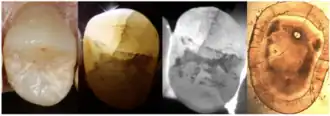

Dye Test

3. Dye Test

Dye application, using agents such as methylene blue can enhance the visibility of cracks (Yu et al., 2022). The dye test is limited in that it can only locate cracks but not assess their progression. Additionally, bacterial infiltration of cracks can cause discoloration that is difficult to remove, affecting aesthetics and treatment outcomes.

4. Transillumination

Transillumination involves using fiber-optic light to illuminate the tooth surface, with light diffraction at the crack helping to locate it (Chanchala HP et al., 2022).

Microscopic Detection

5. Microscope detection

Cracks with width less than 18 μm are difficult to detect with the naked eye, making dental microscopes an essential tool for crack identification.